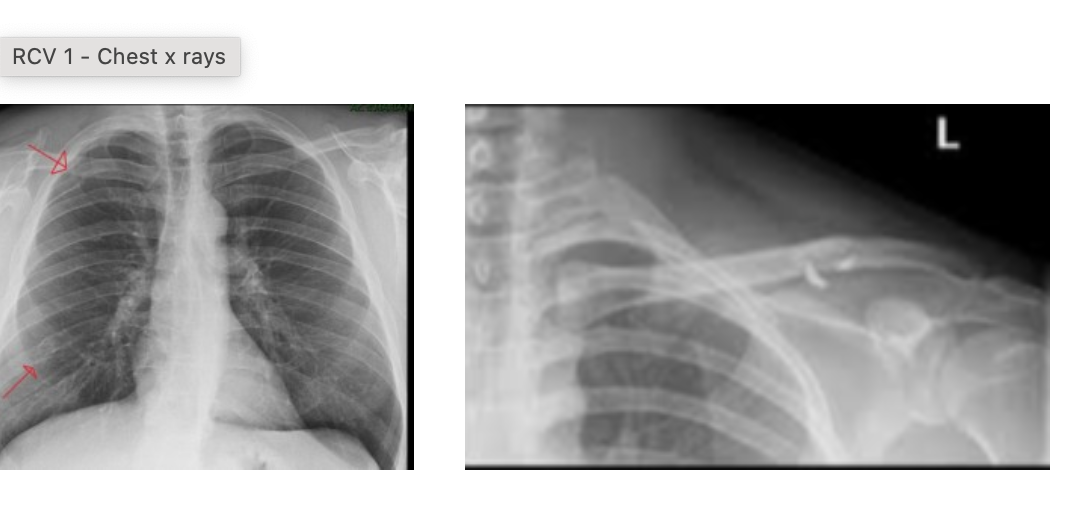

what would a Lower lobe collapse look like on an xray?

A

-increased opacity

-loss of silhouette

22